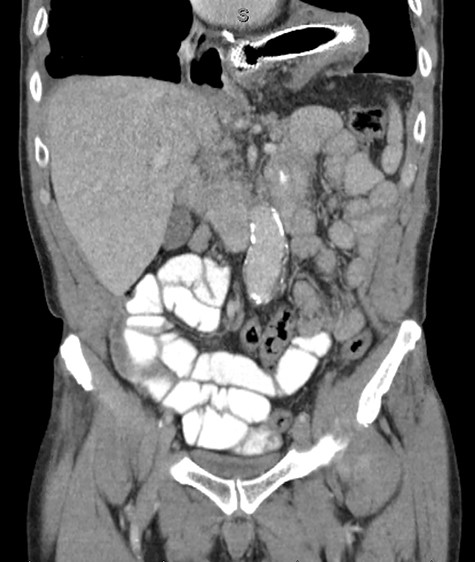

Unfortunately, 6 weeks thereafter he returned with 5-day history of significant abdominal discomfort. He reported tolerance of oral diet without nausea or vomiting. Vitals and laboratory results were unremarkable. However, on computed tomography (CT), initial SEMS had migrated to the transverse colon that herniated into the thoracic cavity via enlarged hiatus (Fig. 6). He underwent upper endoscopy the following morning to ensure the initial stent had not eroded through the gastric conduit into the adjacent colon, as well to ensure adequate positioning of the second stent. Colonoscopy subsequently then proceeded. Although technically difficult the migrated stent was identified and removed with rat-toothed forceps (Fig. 7). His post-procedural course was without complication and he was discharged home the following day with symptom alleviation.

Coronal CT identifying SEMS within the transverse colon, herniated into the thoracic cavity.